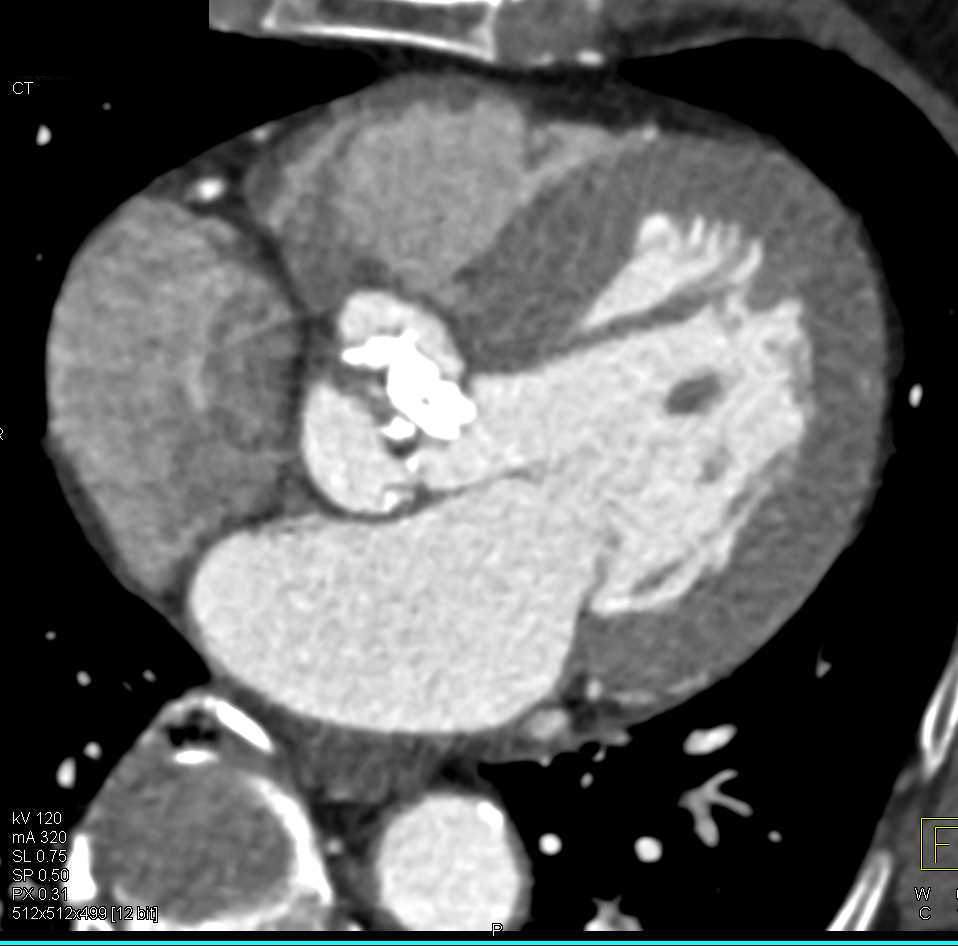

Failed Endovascular Stent